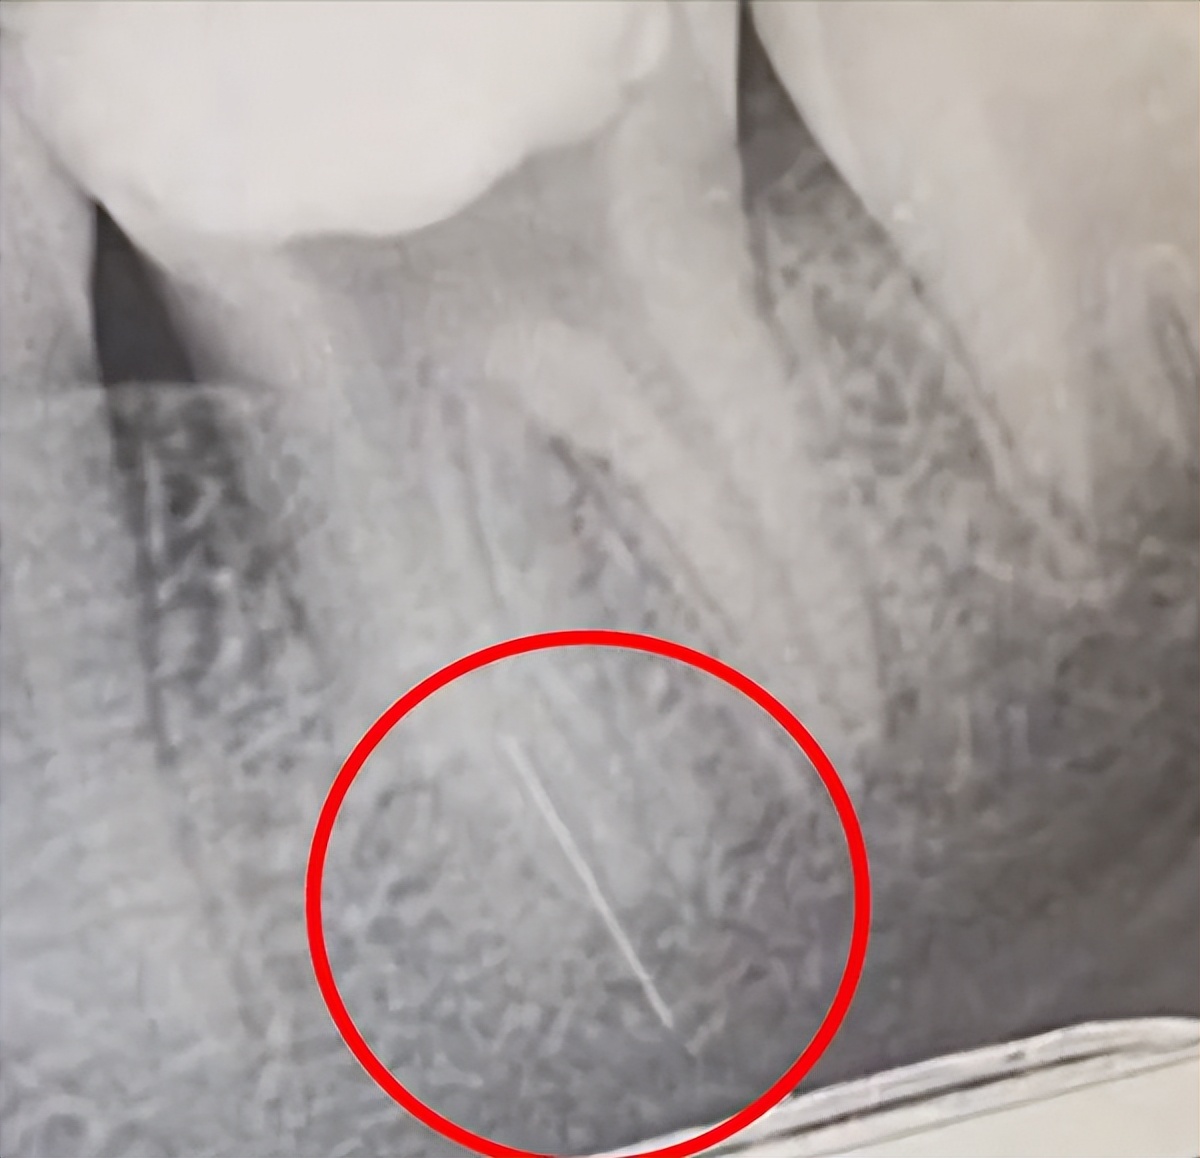

上个月,她带着年仅13岁的女儿去医院做根管治疗,第一次去还好好的,结果第二次去的时候却被医生告知: 做根管治疗的针管断在牙齿里了。

唐妈妈看到医院提供的X光片时,只觉得脑瓜子嗡嗡的,因为 断掉的根管特别长,而且离神经特别近,这要是有个万一......

但这种情况,一般是需要断针位于牙体下三分之一,但未超出根尖孔才行,上文案例中,从X光片可看出, 断针已经刺穿了牙体,超出了根尖孔 ,这种情况直接封管填充,多多少少有些碰运气的成分在里面,因为 一旦引起炎症,这颗牙大概率难以保留。

像前文13岁小女孩这种情况,其实目前来说确实是最佳的处理方式,因为断针太长,而且位置极深,取出难度极大,甚至可能需要拔除牙齿。老黑相信,老教授决定封管,一定是因为目前女孩并未出现炎症反应, 且断针和牙神经并没有处在同一水平面 ,不会对神经造成影响,只要后续没有并发炎症,也不会对小女孩的健康造成任何影响。